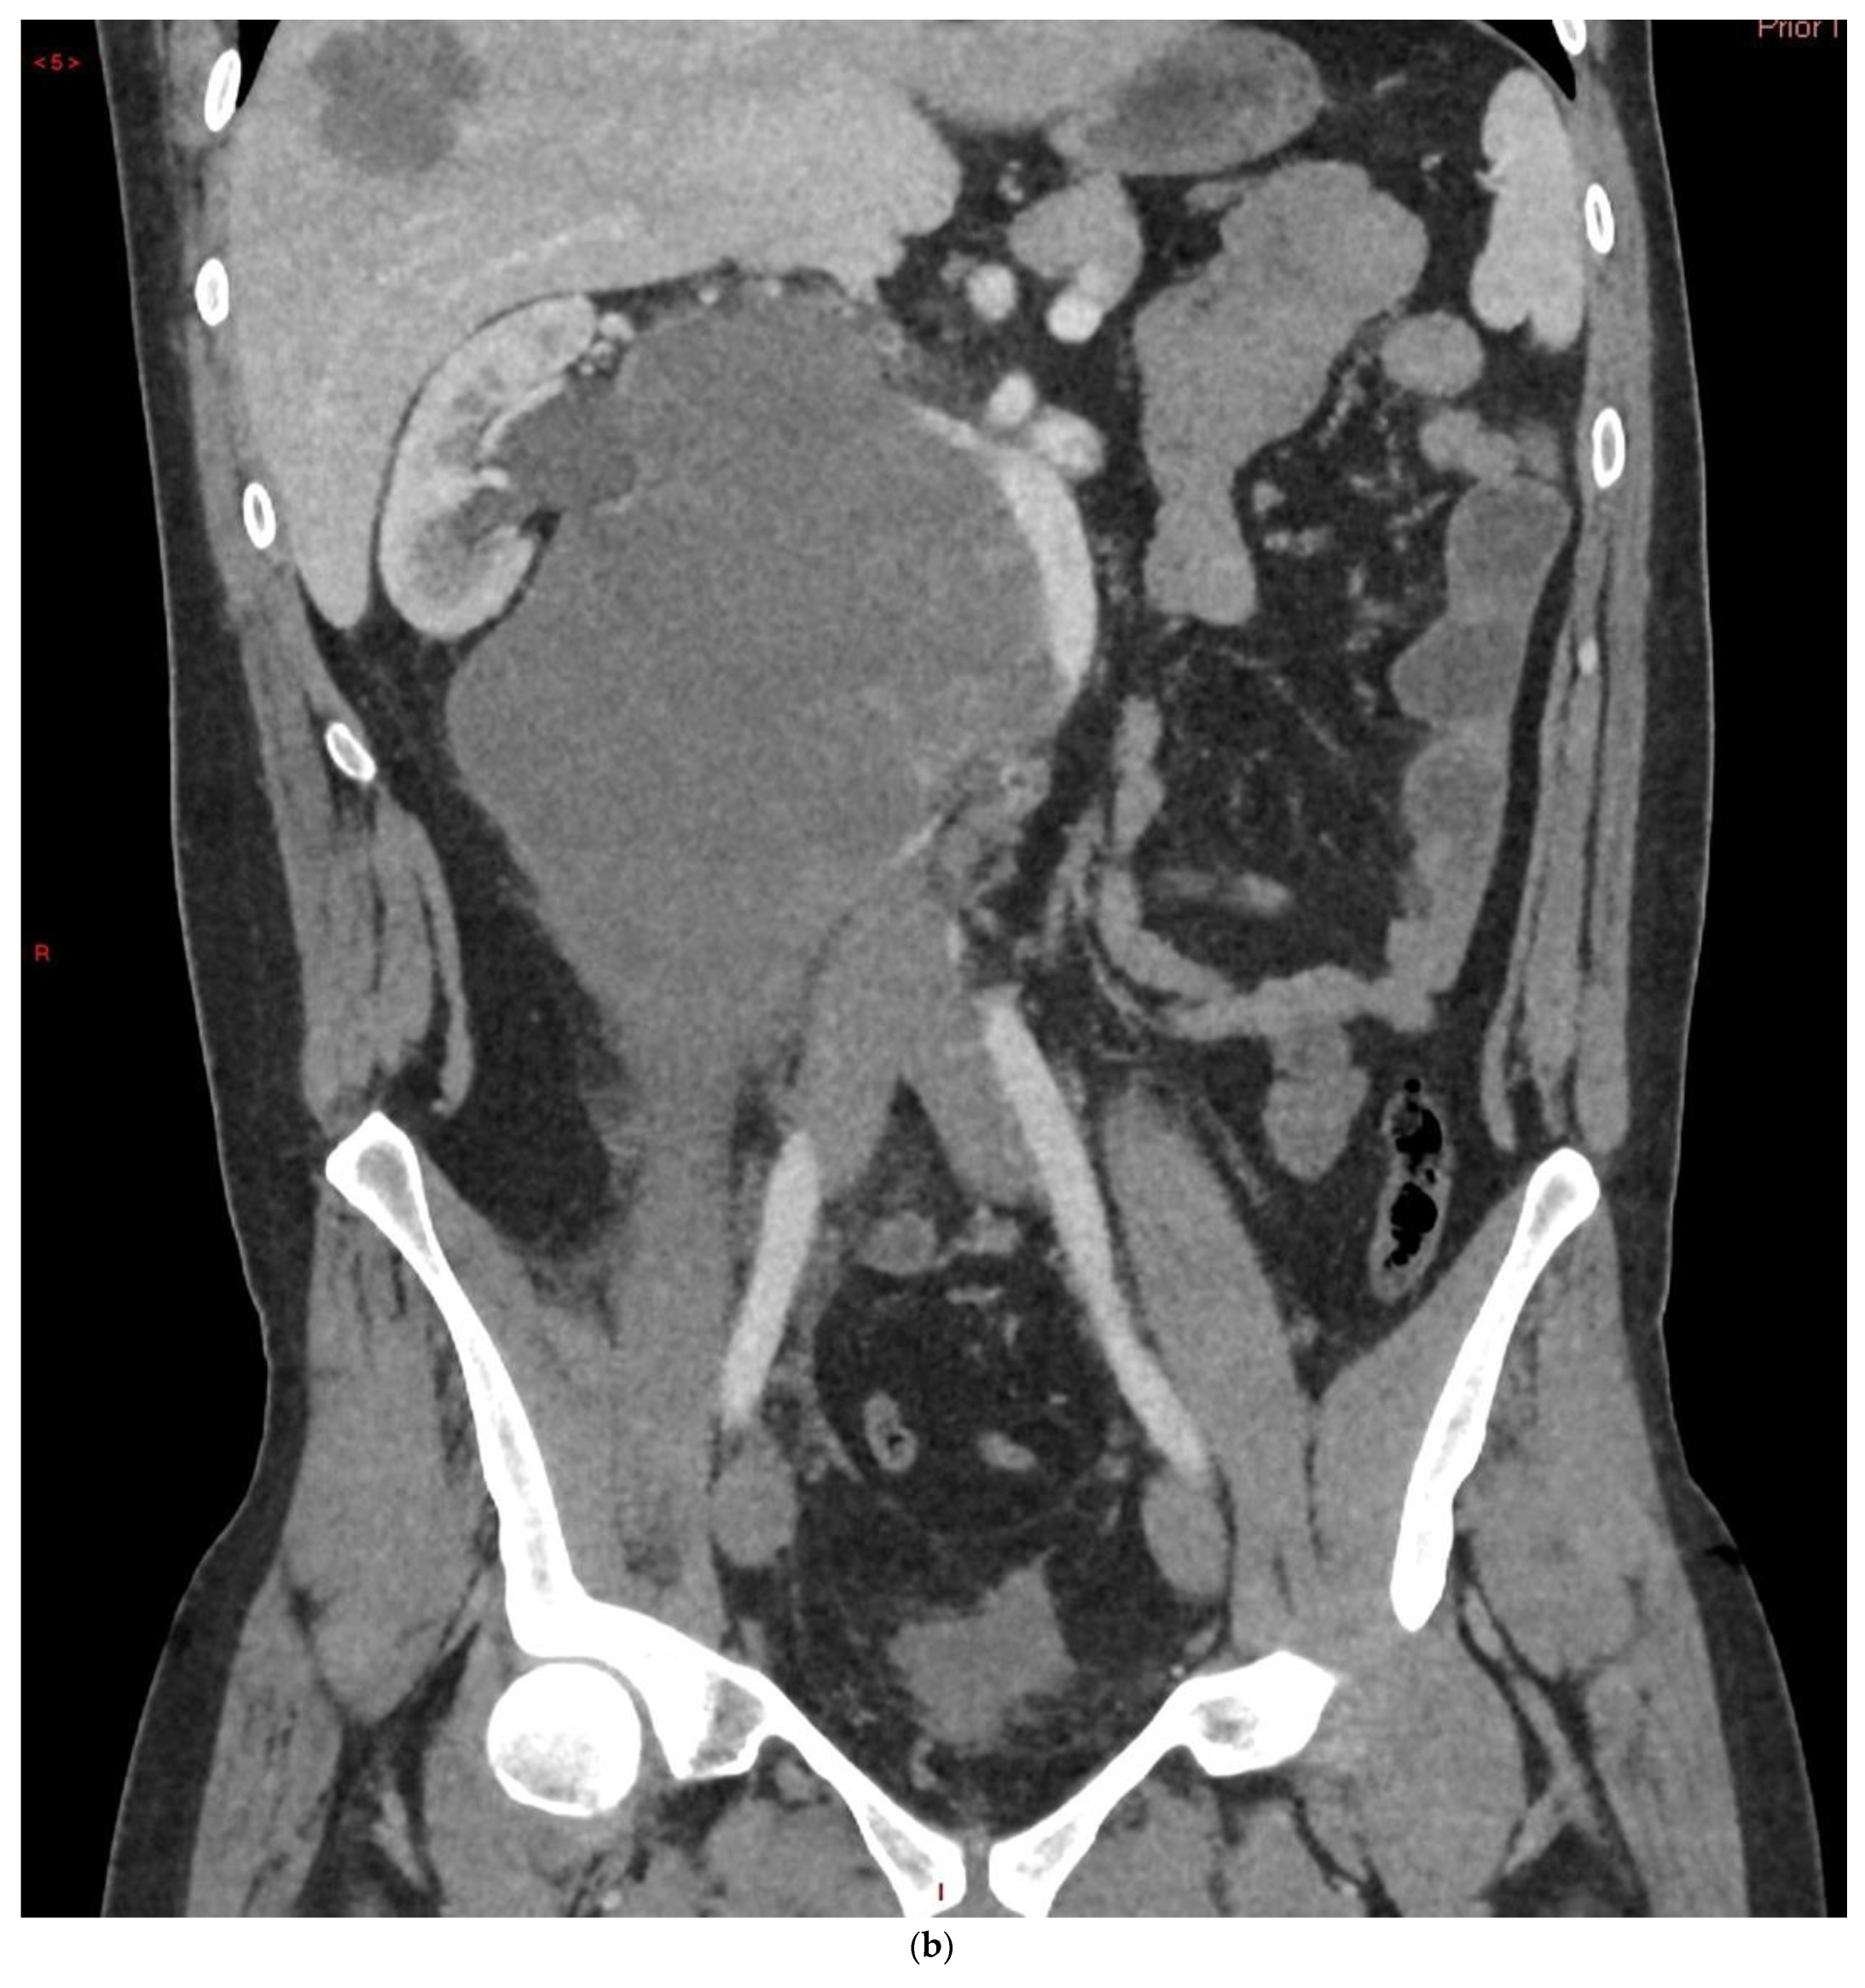

4.1. Seminomatous Germ Cell Tumour

4.2. Non-Seminomatous Germ Cell Tumour (NSGCTs)